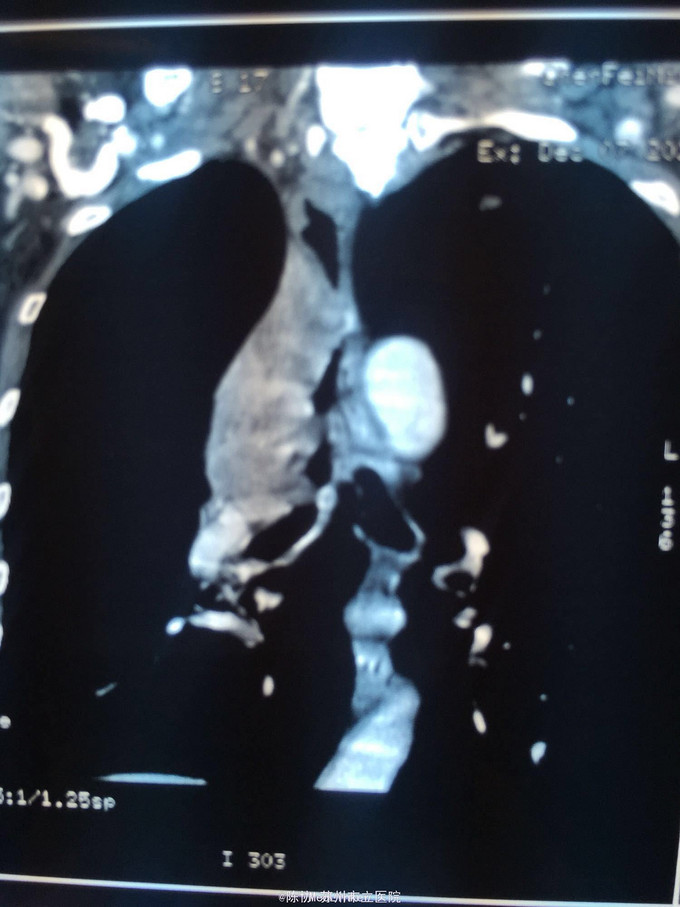

主诉:体检发现右上肺不张半月 77岁男,半月前体检发现右上肺不张,无不适。无消瘦,无咳血,无干咳。去年4月右上肺炎,抗生素治愈,当时CT未见肺肿块。入院支气管镜发现右上支气管开口组织增厚闭塞,开口近侧有隆起约3x3平方毫米,取活检5块病理示中度非典型增生。CT提示在右侧主支气管外侧有30x30平方毫米块影,压迫右上支气管开口处。三大常规和生化检查正常,肿瘤指标正常,TAP正常。

右侧中央型肺癌 重做支气管镜,精于定位找到病症组织,获得病理诊断来指导治疗。 胸外科医生不建议手术,理由是肿瘤位置靠近主支气管和气管,袖状切除不一定看干净。 请问正确的诊断,和比较合理的治疗方法是什么?求助大家思考评论